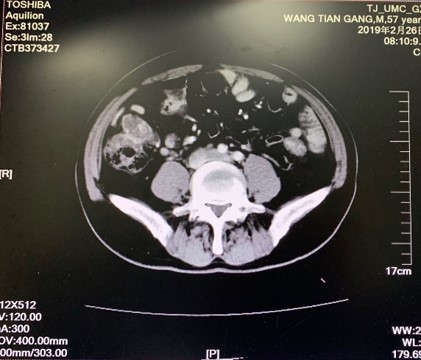

2019.2.26复查

胸CT示:右心隔角区多发增大淋巴结。

全腹强化CT示:右侧心隔角、腹盆腔腹膜及腹膜后多发转移性病变较2018年08月增大。